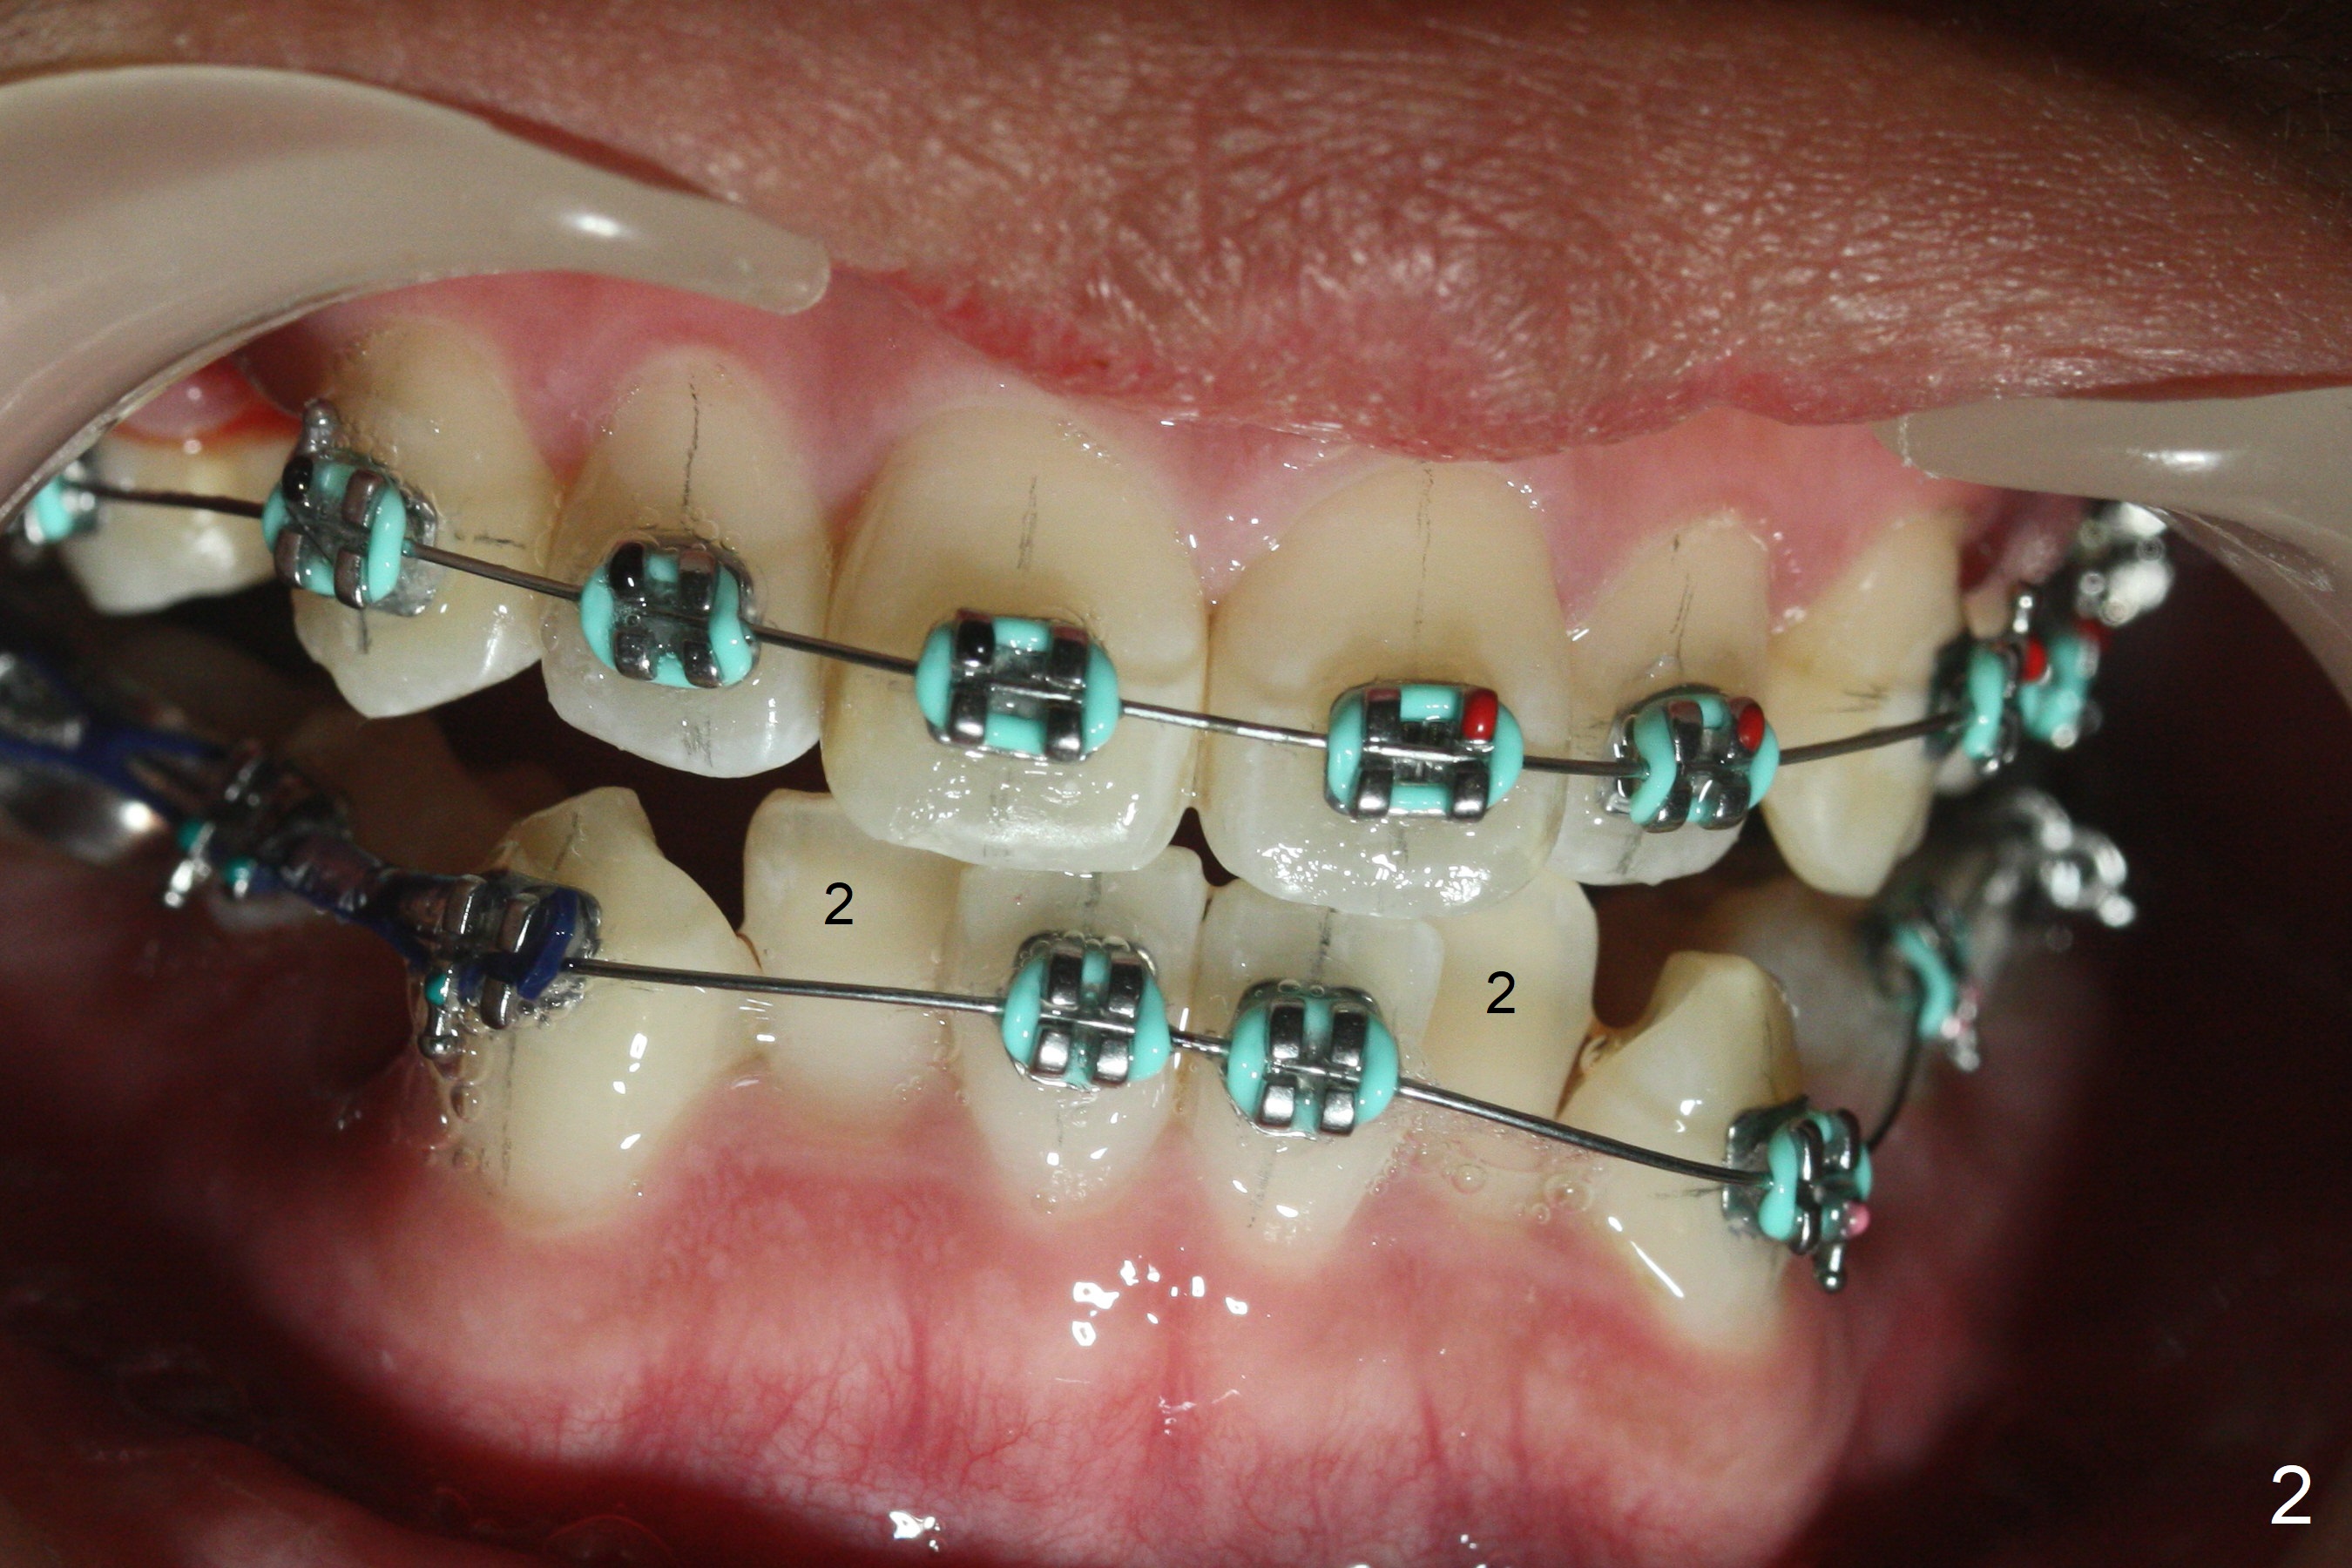

Twelve months post extraction and banding, there is anterior overjet. A posted wire is used to retract the upper incisors for a month. It appears that the upper midline deviates to the right (Fig.6, as compared to Fig.5 (pre-treatment)). Closed coil spring is removed on the right in hope that the upper midline will shift to the normal by the left coil spring (Fig.7-9). Is there a better alternative? There is mild root tip resorption 2 years 1 month post banding/immediate post debanding, as related to extraction ortho (Fig.10).